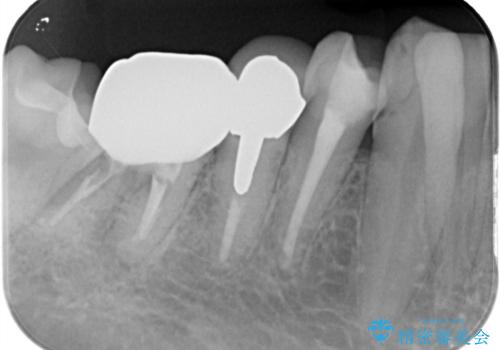

- フロスをしていたが歯と歯の間にはさまり、取れなくなったとのご相談にいらした患者様です。以前、他院で治療した部分に凹みがあり、その部分にフロスが残留しちぎれていました。このため、根本的に歯のかぶせ物・詰め物を新しくする必要があると判断いたしました。治療後はフロスでのケアもスムーズになり、良好な経過をたどっています。

一般的に、失活歯(根の治療をし、神経を取り除いてある歯)はそうでない歯と比較し、噛み合わせの力がかかりやすいといわれています。残存する歯質の量にもよりますが、歯の破折を防ぐためにクラウン(かぶせ物)を選択するケースが多いです。